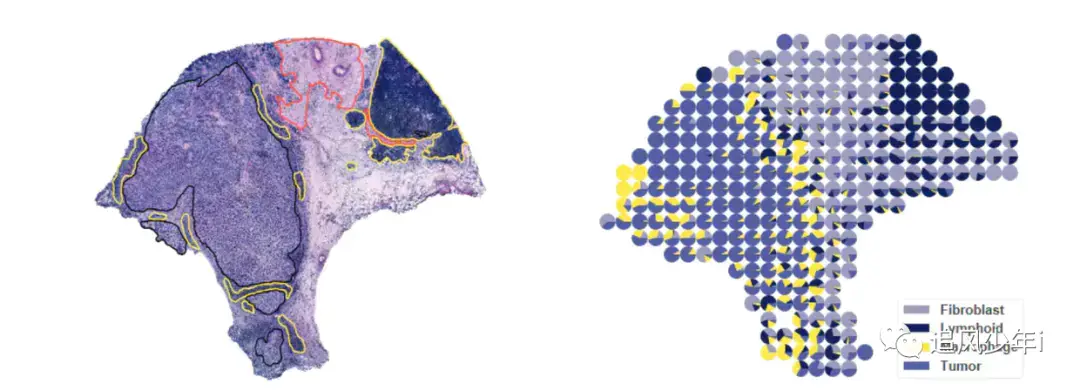

最近一直有人问我空间转录组的饼图该如何绘制,如下图

相信大多数还是利用Seurat来进行联合分析,如果用了其他软件,可以将联合的矩阵结果进行替换,我们还是以之前的结果为例,HE染色和单细胞空间联合分析的结果部分展示如下

画出来的效果如下图,颜色根据自己的喜好进行搭配

好多了,借鉴一下第一张图的搭配

来对比一下其他文章的图片形式